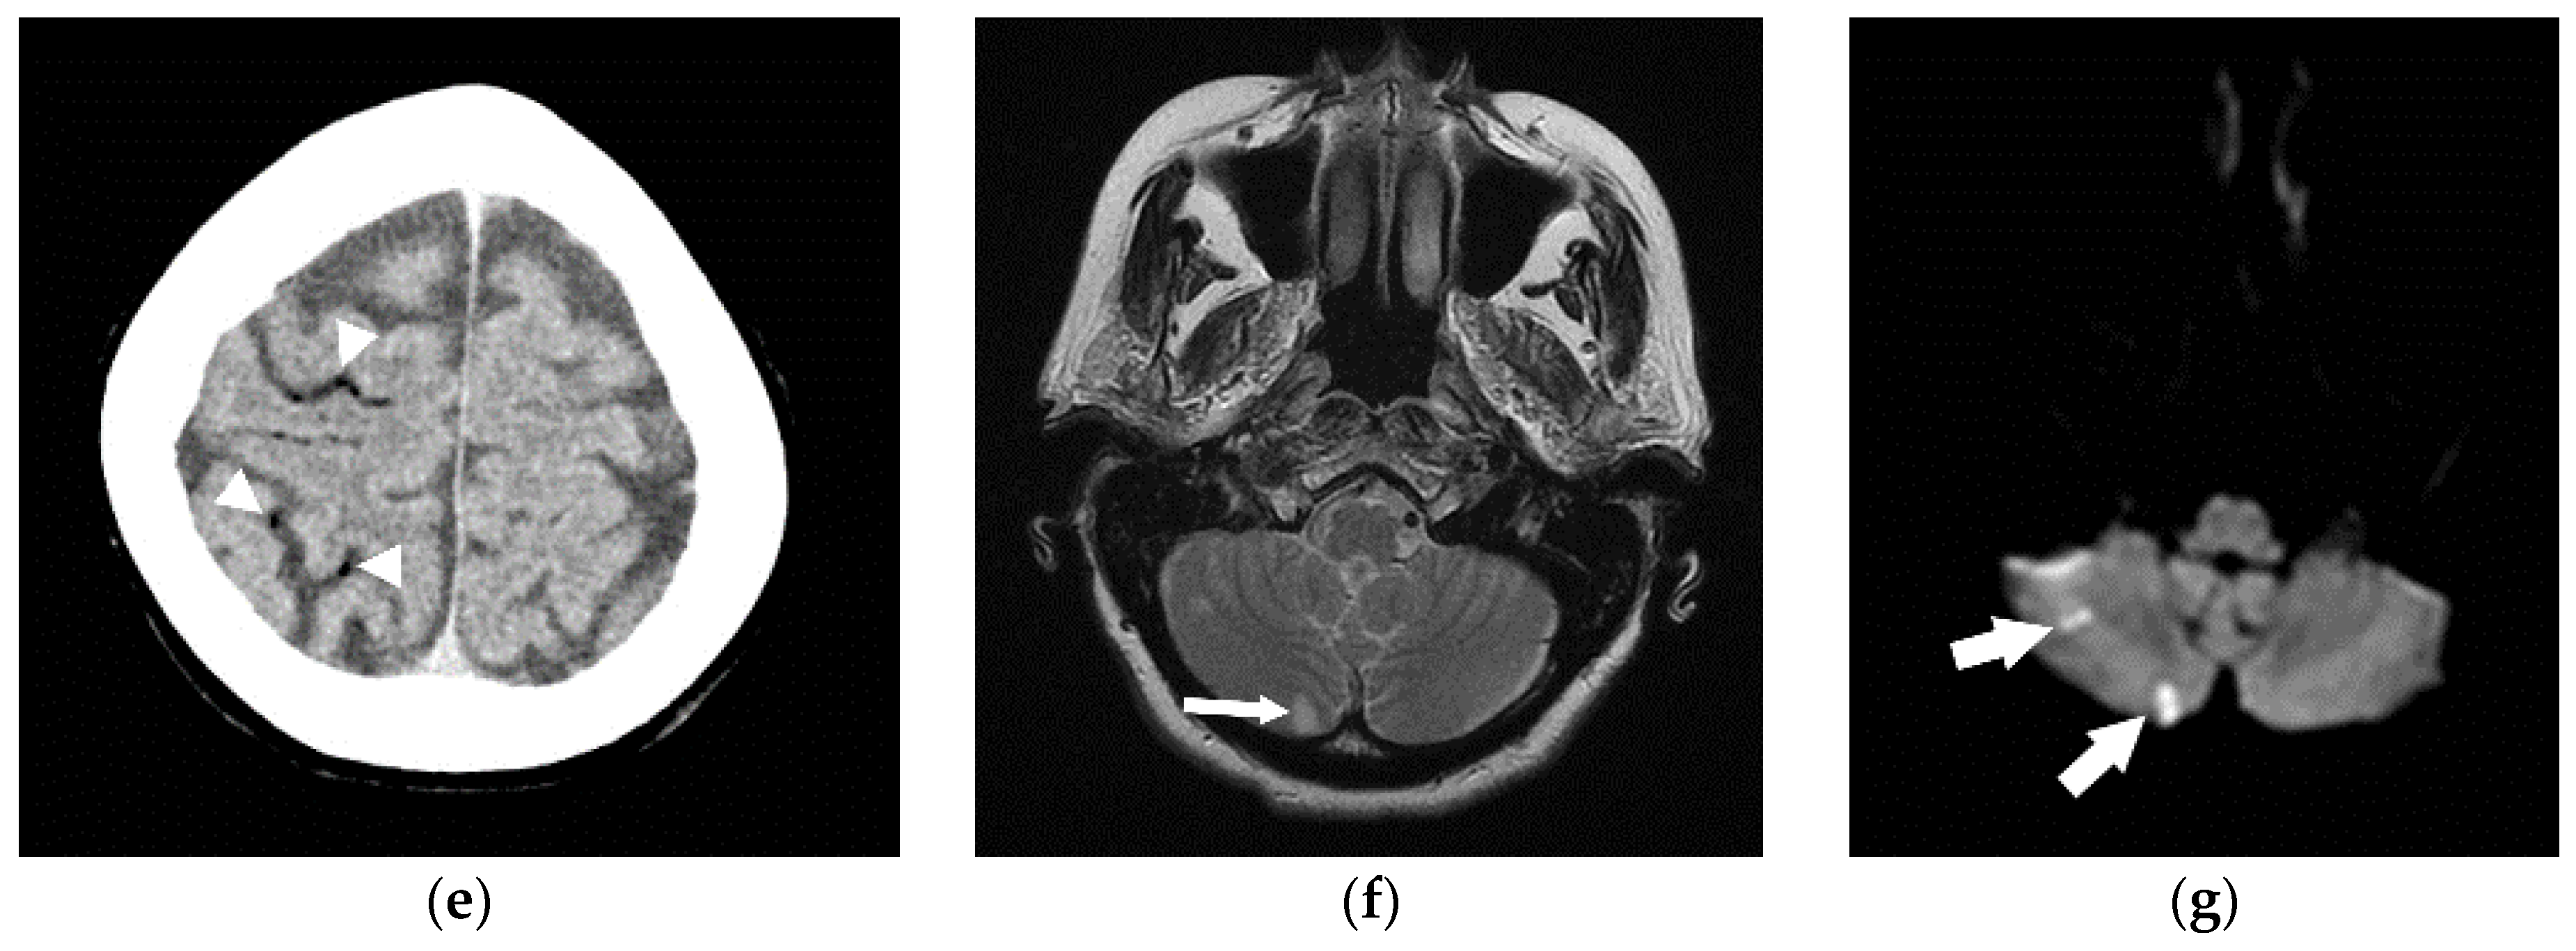

Figure 9.

A 68-year-old woman underwent cerebral angiogram (a) for evaluation of 3 cm left cavernous internal carotid artery aneurysm (*). Post procedure, she developed transient aphasia, right facial droop, and right arm brachyplegia likely secondary to air embolism. This was presumed to be related to faulty occlusion balloon. The patient was immediately placed in a cervical collar to minimize head movements and distal air embolization as well as started on 100% oxygen therapy. Hyperbaric chamber therapy was discussed but declined due to concerns about patient movement during transport. CT angiogram (b,c) was performed immediately. Post-procedure revealed air within the large left cavernous segment internal carotid artery aneurysm (arrow). A CT performed 2 days later (d) showed the embolism had resolved and this patient made a full recovery.